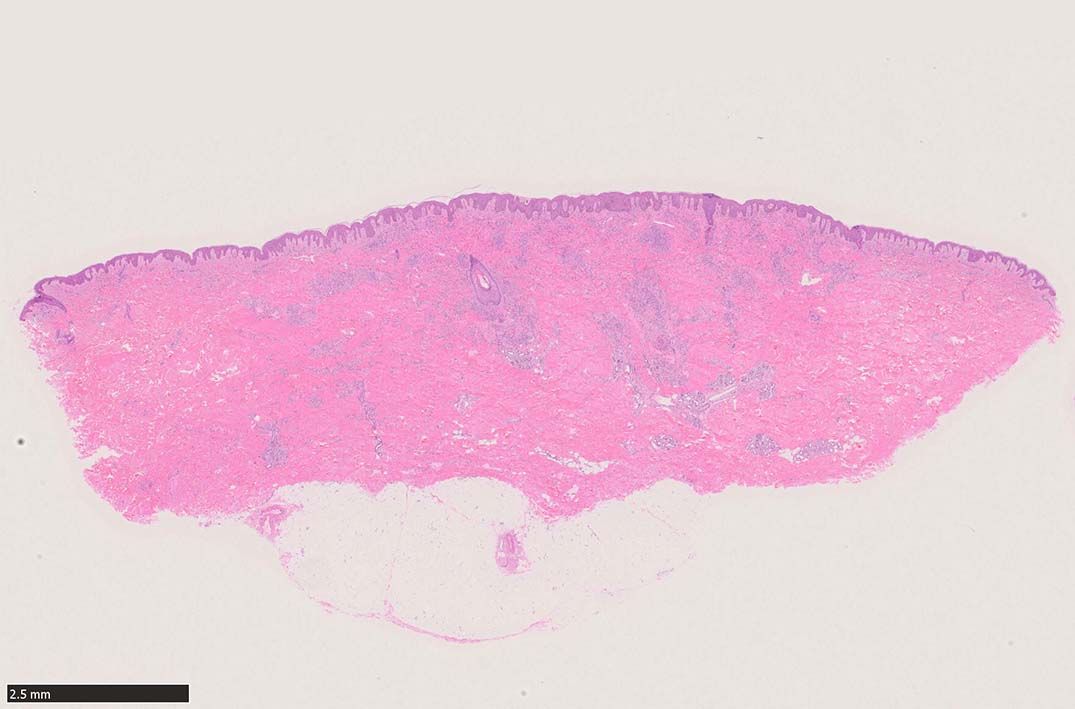

肉眼で平坦な斑状(macule)病変 --> 平板にやや盛り上がった隆起; 局面(plaque)病変 --> 更に進行し結節状(nodule)病変に進行する. (病理所見も病変の進行とともに変化している.)

初期斑状病変の病理

初期の斑状病変の組織学的所見はごく軽度の炎症反応の様相を呈し, 真皮内の正常毛細血管を囲むようにして拡張した血管内皮様細胞による管腔が認められる.

好中球などの炎症細胞浸潤はまれであるが, 形質細胞はしばしば増加している.*5

この時点ではKaposi肉腫特有の線維芽細胞様紡錘形細胞(spindle cells)は少なく, 診断はときに困難である. (HHV-8免疫染色が必須)